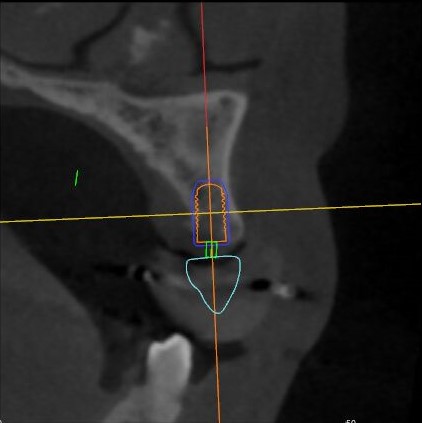

觀察患者CT,可看出患者有上頜竇粘膜囊腫,粘膜囊腫為竇內(nèi)腺體阻塞所致,視情況可有手術(shù)摘除和不予處理兩種方法,此次患者拒絕手術(shù)摘除,故需規(guī)避上頜竇位置。

根據(jù)患者CT顯示,使用種植導(dǎo)航軟件設(shè)術(shù)前手術(shù)方案??紤]到患者拒絕手術(shù)摘除上頜竇囊腫等因素,此次手術(shù)選用了Straumann骨水平4.10*8.0mm的植體,植體末端位點(diǎn)設(shè)計(jì)距上頜竇底壁2mm處的同時(shí)兼顧種植方向和修復(fù)間隙,來(lái)達(dá)到理想的效果。

從術(shù)后CBCT顯示可以看出,手術(shù)操作中完美地避開(kāi)上頜竇底,并兼顧了正確的種植方向和修復(fù)間隙